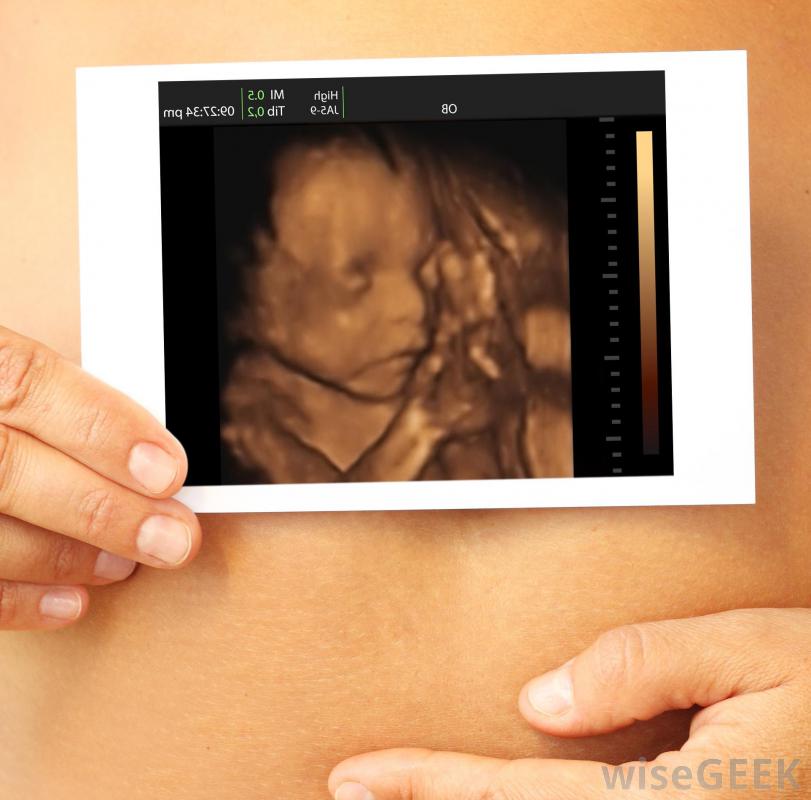

超声波可用于检查胎儿发育。

产前超声检查。

超声照片有助于让怀孕的夫妇真正怀孕。